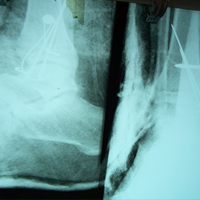

Case:14 Periprosthetic Fracture

60 years old patient with total knee replacement on left knee presented with open grade 1 injury. Debridement & slab given on emergency bases. Fixation with plate & screws done. Union was seen after 6 months.

Pre-Op AP

Pre-Op Lat.

Immdiate Post-op